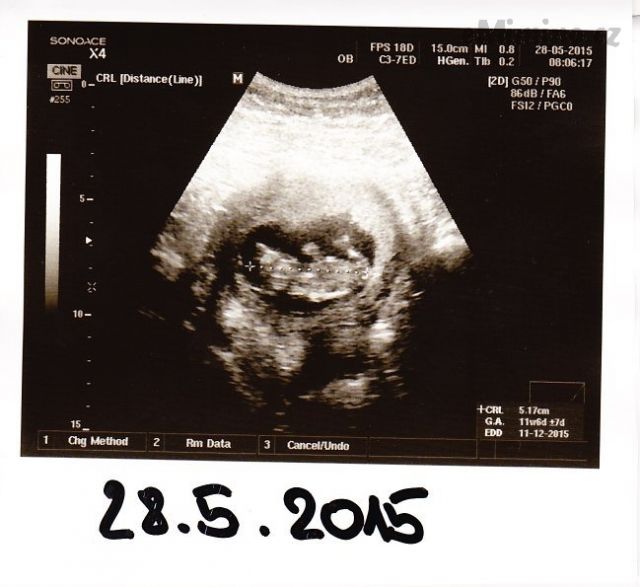

28. května 2015 (11+4)

– první miminko 11+6, 5,17cm

– druhé miminko 11+4, 4,82cm